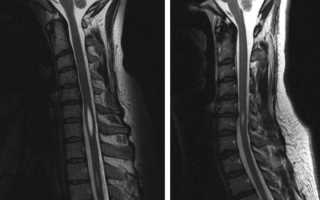

Для установления точного диагноза необходимо обратиться к врачу-неврологу. Этот специалист основывает свои выводы на данных, полученных с помощью компьютерной и магнитно-резонансной томографии. Исследованию могут подвергаться различные отделы позвоночника: грудной, шейный, а в редких случаях и поясничный.

Диагностика сирингомиелии обычно включает в себя магнитно-резонансную томографию (МРТ), которая позволяет визуализировать наличие кист в спинном мозге. Также могут быть проведены неврологические тесты для оценки функции нервной системы.